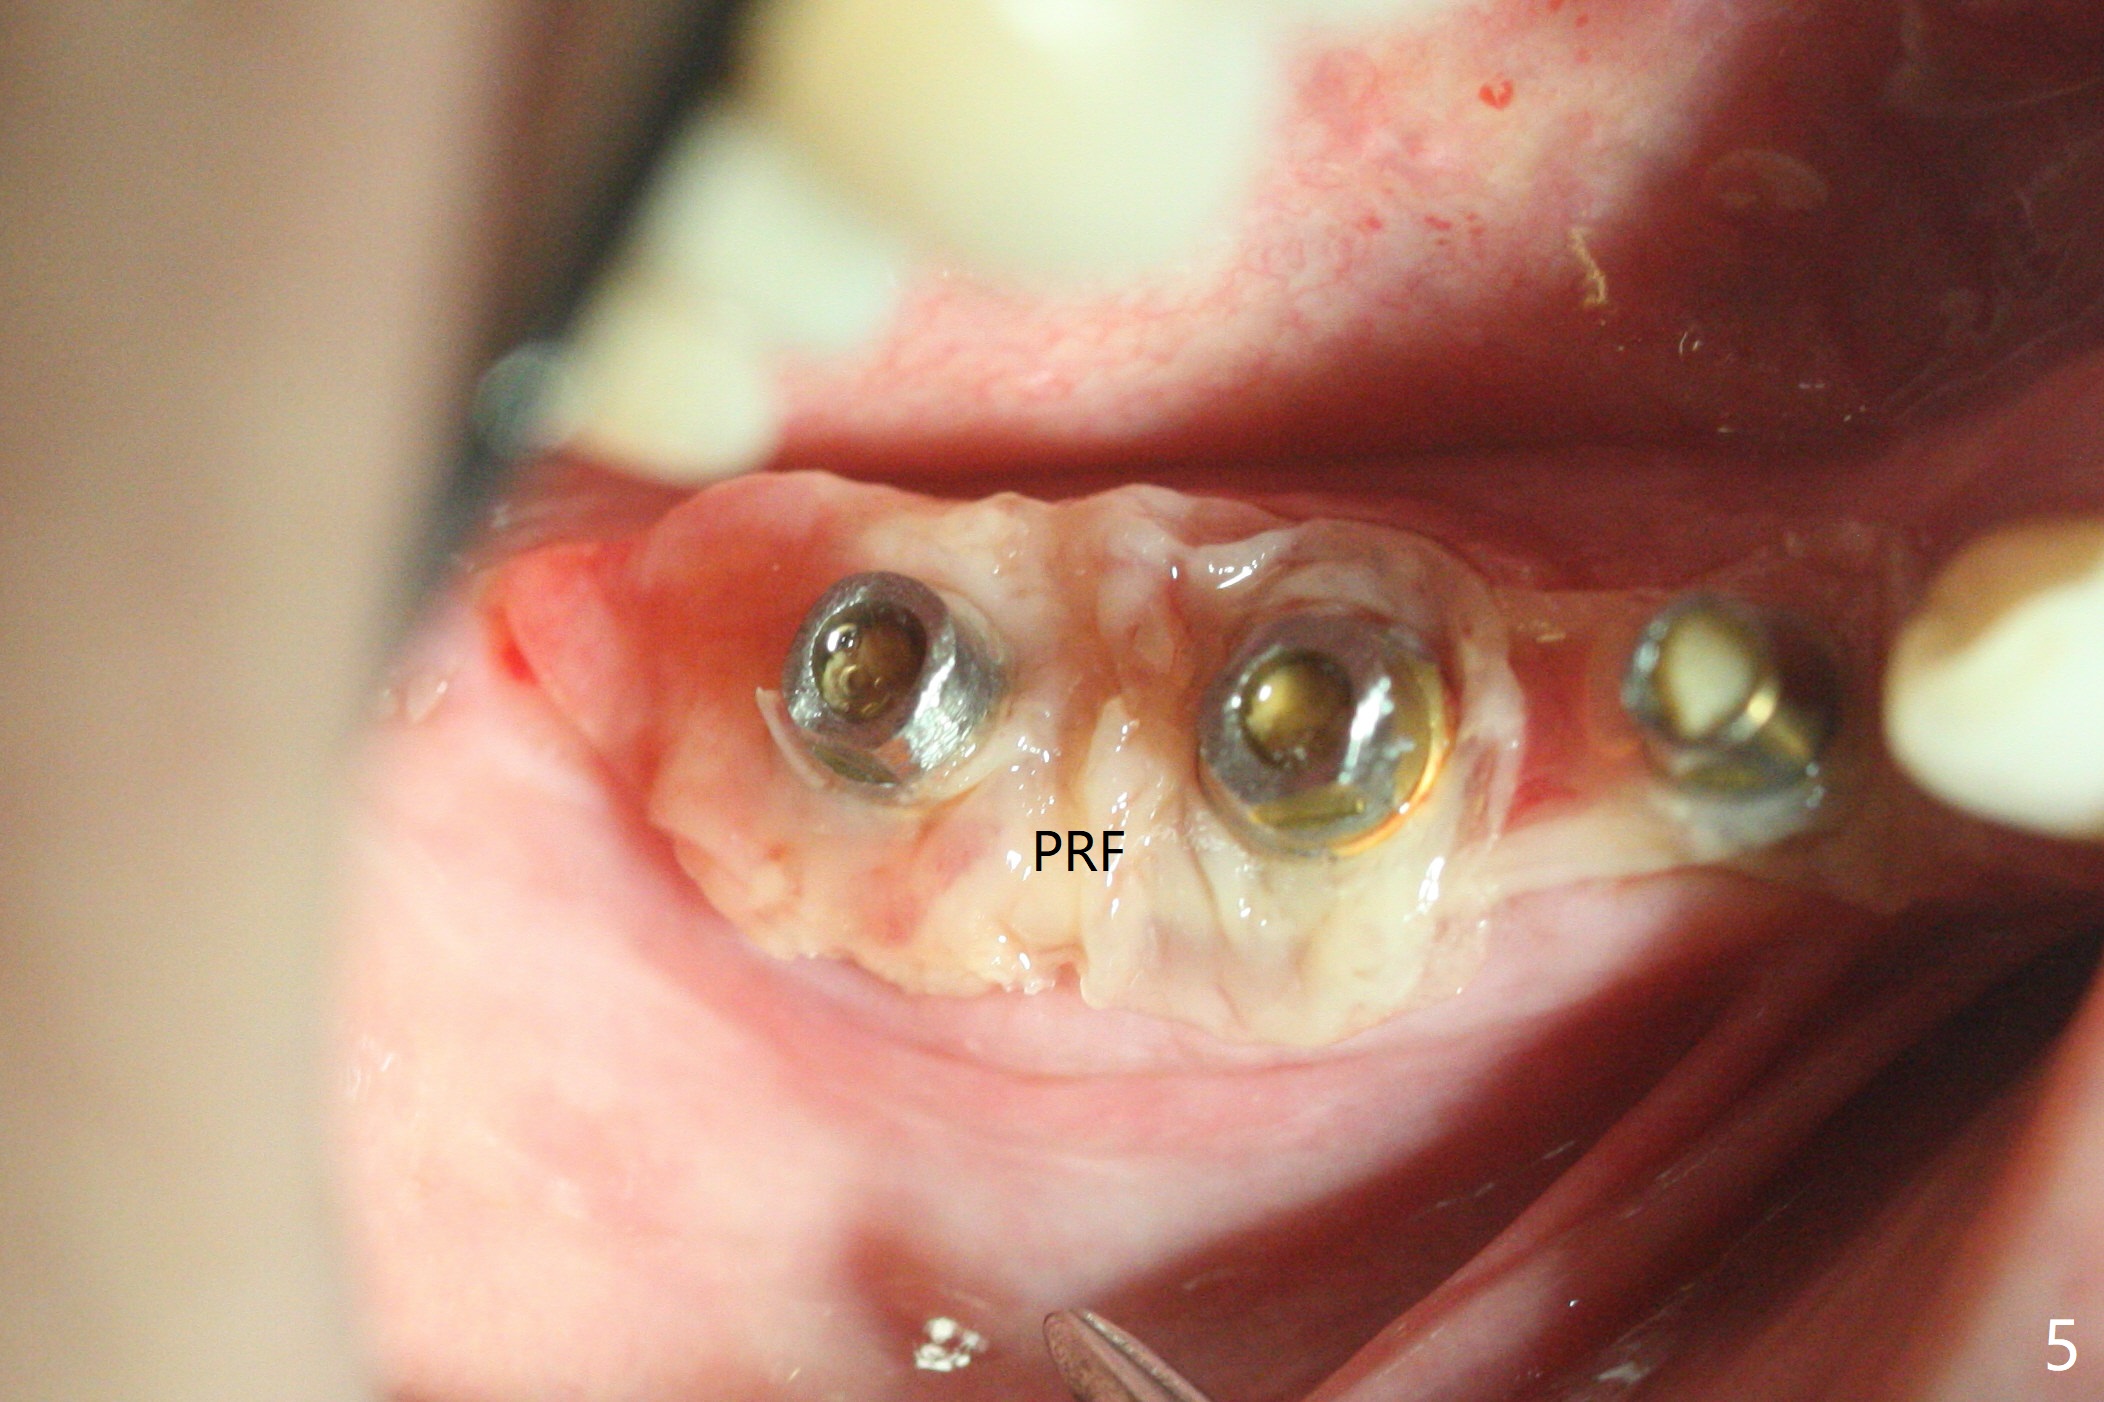

右下4-6种植后3.5月制作临时牙桥(保险的钱用完了),虽然不舒服,病人也没有及时复诊。新年过后(术后11月),她回来修复,但是临时牙桥下沉,造成牙龈退缩(图一),6螺纹暴露(图二:>),粘性骨粉中间形成一个洞眼(图三),插入6基台固定(图四),同样PRF膜也形成两三个洞眼固定在基台上(图五)。当粘性骨粉放置时,暴露螺纹已经被血凝块覆盖,舍不得去除,所以骨粉就不能接触螺纹(图六),最后用牙周敷料固定(图七),想象比树脂敷料服帖。不过2天后,牙周敷料脱落,骨粉丧失,伤口好像已经愈合(图八),没有做任何处理。今后类似病例应该在基台上涂抗病毒凡士林(以后好撤除),使用树脂敷料。Return to No Deviation Xin Wei, DDS, PhD, MS 1st edition 01/05/2021, last revision 01/08/2021